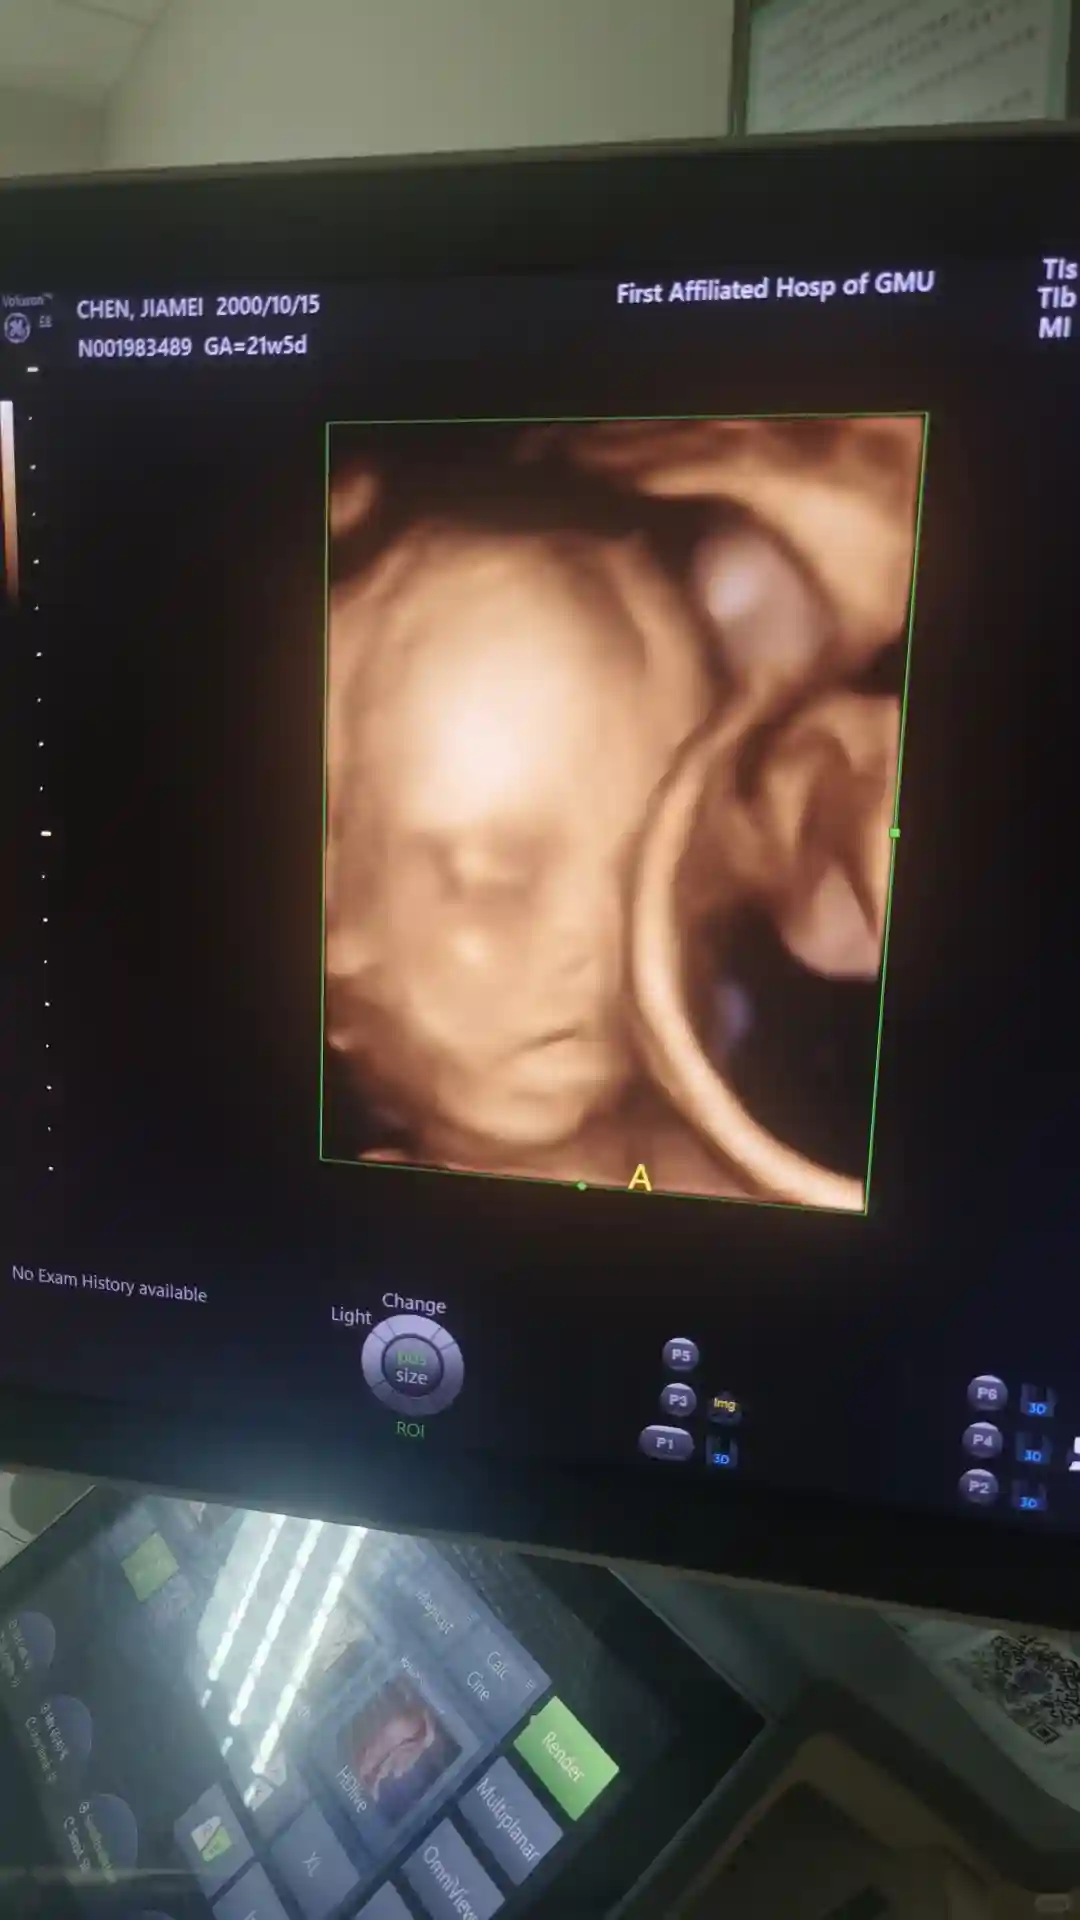

调整方案 第三次移植两枚胚胎 终于成功 前期血值翻倍不好很焦虑 都是胡主任的一句 没事有我在该用的药都用上了 接下来的就是要相信自己相信宝宝 因为离得离医院近 胡主任称得上是我的定海神针 经常有事没事跑去找主任聊聊天 天天问一大堆罗里吧嗦的问题 也从来不嫌烦 称得上是“老油条”了 正常情况一般12周左右就生殖科毕业 我一直都有各种各样不一样的问题硬生生的拖到16周才彻底毕业 回家之前主任也给我开好了各种防宫缩止血的药 所以有的时候想想能遇到一个有责任心的医生真的很幸运

接下来就希望我的宝宝能够健健康康出生 等他们满月之后带他们"回家"去看看